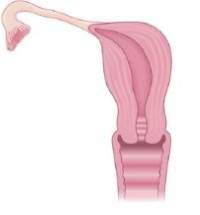

Utérus Unicorne